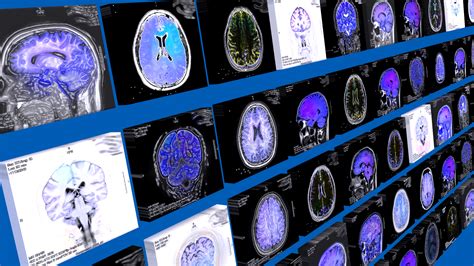

Diagnosing CMID involves a comprehensive evaluation of the patient's medical history, physical examination, and various diagnostic tests. The diagnostic process may include:

• Imaging Studies: Magnetic Resonance Imaging (MRI) and Computed Tomography (CT) scans to visualize the brain and detect any abnormalities.

In some cases, additional tests such as positron emission tomography (PET) scans or single-photon emission computed tomography (SPECT) scans may be used to assess blood flow and metabolic activity in the brain.

• Imaging Techniques: Developing advanced imaging techniques to better visualize and assess brain ischemia.